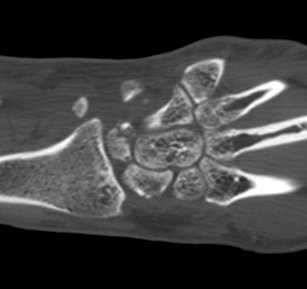

ÄÄÇ»ÅÍ ÃÔ¿µ :  ¿ù»ó°ñÀÇ ºÐ¼â°ñÀýÀÌ °üÂûµÊ(»çÁø 5, 6, 7, 8).